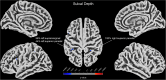

Results: Compared to participants in the PWH control group, those in the PWH-DD group showed higher scores in evaluation of depression, anxiety, sleep disturbances, childhood trauma, and mental health symptoms, indicating a greater burden of psychological and emotional distress. Comparisons of brain structure showed that participants in the PWH-DD group exhibited lower GMV in the left middle frontal gyrus, shallower sulcal depth in the left supramarginal and bilateral superior parietal regions, and lower fractal dimension in multiple frontal and temporal lobe areas compared to those in the PWH control group. Among all participants, correlation analysis demonstrated that GMV of the left middle frontal gyrus was significantly negatively correlated with Self-Rating Depression Scale scores.